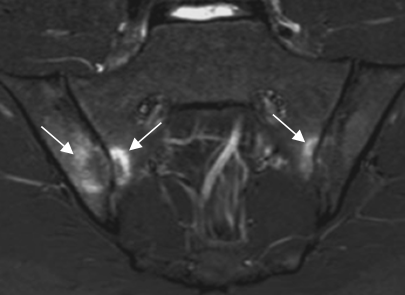

Fig 58 C. Espondilitis anquilosante.

A y B: RM coronal en STIR. Lesiones agudas bilaterales, en A. Si solo se encontrara la lesión del lado izquierdo, esta tendría que verse en 2 cortes consecutivos, para ser considerada positiva. (Flechas delgadas).

Fig 58 D. Espondilitis anquilosante.

A y B: RM coronal en STIR. Lesión aguda derecha, visualizada en 2 cortes consecutivos.